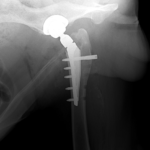

45kgの大型犬が股関節形成不全による痛みがあるとの事。他県より紹介来院されました。KyonのTHRシステム(人工関節)で傷んだ関節を置換しました。関節炎による痛みを感じるのは人も動物も同じです。出来るだけ痛みのない生活を過ごしてもらいたいと思います。インプラントはCup AOL 42° Large STEM 17°、Head19mm、Neck S、29.5 、Cup Anteversion 30°で埋入されています。内科治療に反応のない骨関節炎には人工関節で対応する事も可能です。しばらくは安静が必要です。